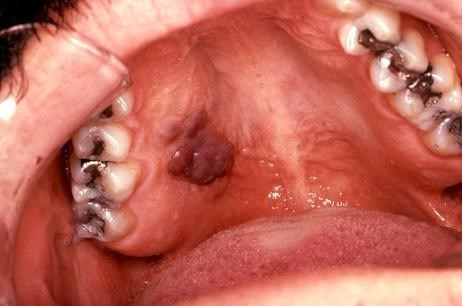

![]() Ung thư vòm họng. Quan hệ bằng miệng sẽ làm tăng nguy cơ bị ung thư vòm họng. Bởi virut u nhú ở người (human papillomavirus - HPV) có thể lây truyền từ người này sang người khác qua đường miệng hoặc qua sự tiếp xúc giữa "cậu bé" và "cô bé".